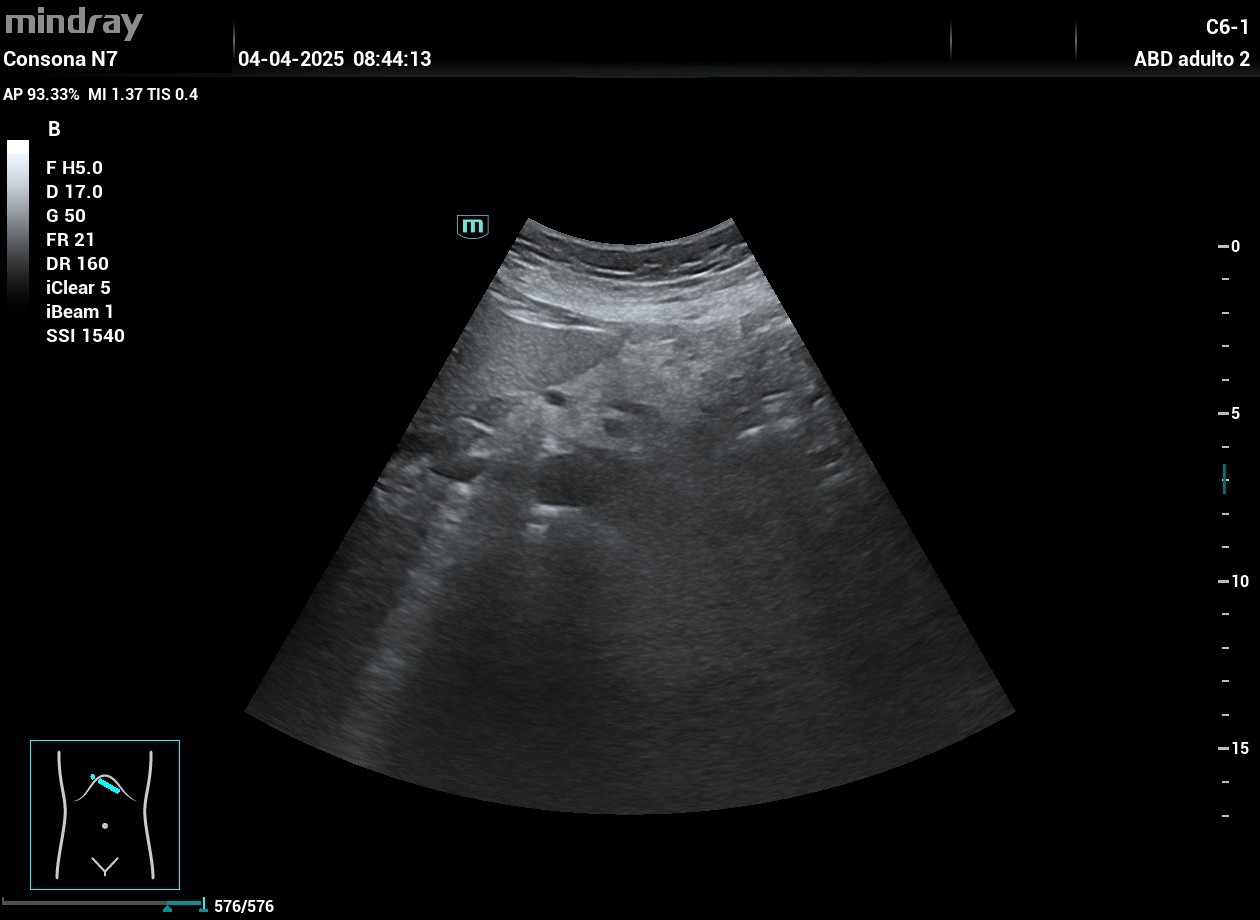

Hallazgos ecográficos

Imagen de ecogenicidad mixta, irregular en cuerpo de páncreas. Ante este hallazgo realizamos una e-consulta al servicio de digestivo enviando las imágenes para su valoración y citaron a la paciente para una nueva ecografía.